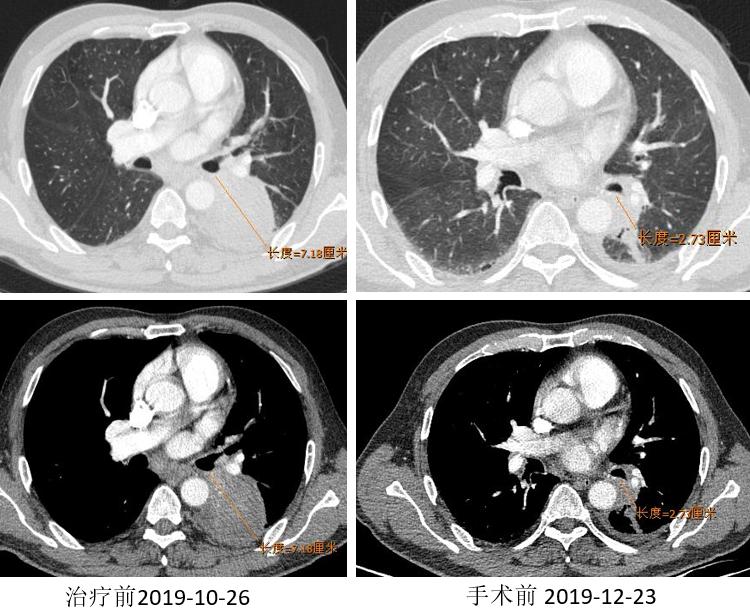

胸部CT

外周淋巴结CT

2019.12.10 行“右肺上叶切除术”。

术后病理:(右上叶)浸润性腺癌(腺管型95%,微乳头型5%),(纵隔4R组淋巴结)阴性。病灶内浸润性腺癌(约占20%),见较多区域纤维化伴组织细胞、淋巴细胞浸润,另见胆固醇结晶、多核巨细胞及肉芽肿反应,符合化疗后反应。